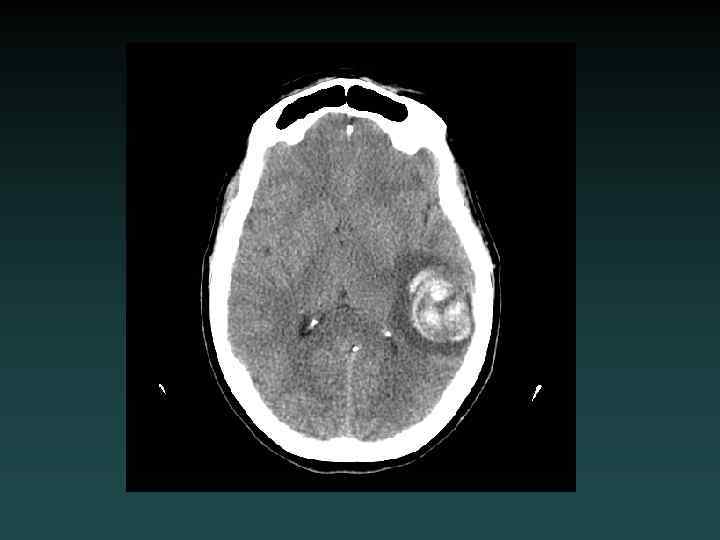

Intracerebral Hemorrhage • Hypertension – Most common – Characteristic Locations • IF LOBAR BLEED: – – SEARCH for underlying cause! MRI/MRA/MRV DSA or CTA Repeat imaging if negative initially • Look for: – EXPANSION – UNDERLYING LESION